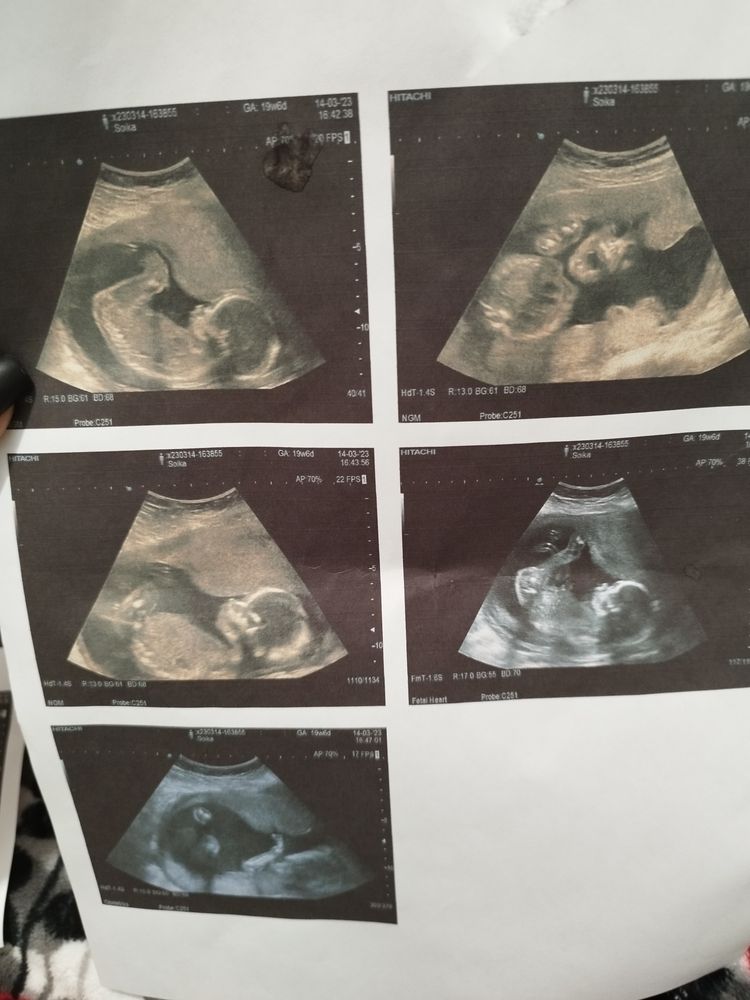

Как думаете кто

Пол малышаПол мы пока не узнаём, через неделю гендер пати...

Но все равно,как думаете кто?? Видно что нибудь?

На первом и последнем фото ножки достаточно высоко подняты должны были быть видны яички , если б был мальчик, так что я думаю 👧